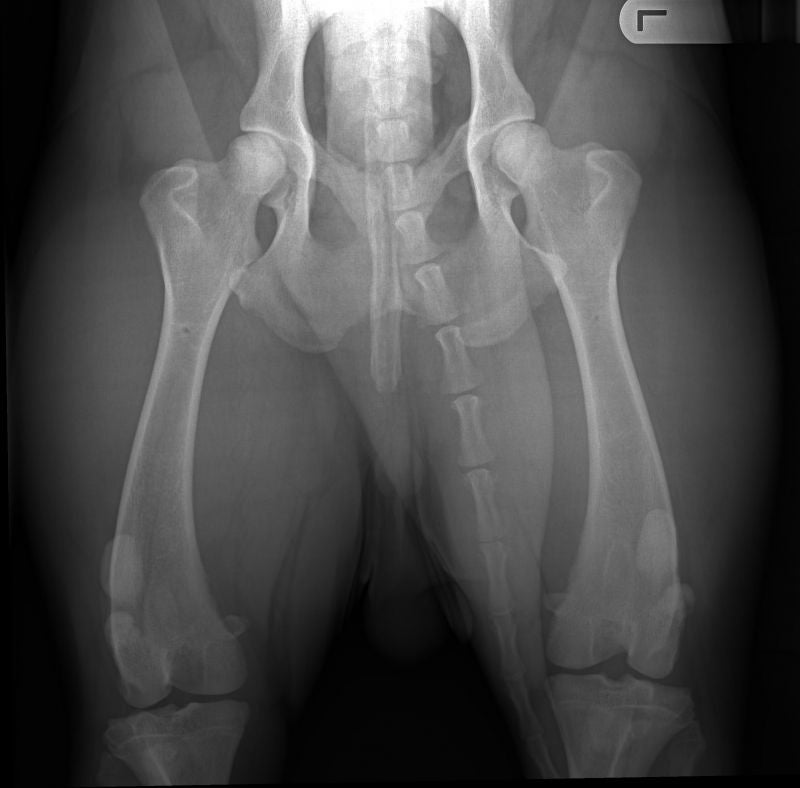

HD-A